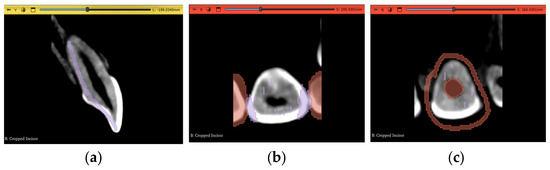

2.3.1. Volume Cropping

2.3.2. Histogram Adjustment

2.3.3. Thresholding Masking